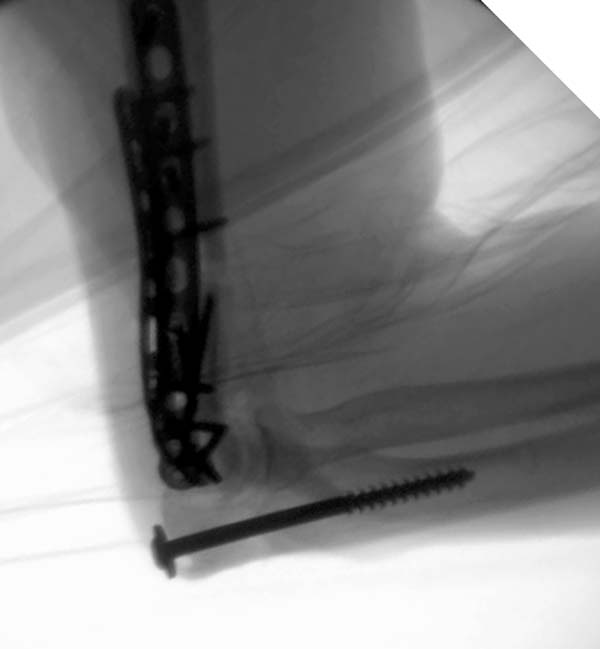

Примеры: первому более 15 лет фиксирован шурупом и tension band

technique, а второй перелом открытый больной 80 лет, после наружного

фиксатора в первом этапе и окончательная фиксация вторично. Третьий раз

внесуставная остеотомия...

Вложение не в текстовом формате было извлечено&hellip;

Имя     : 2-1 Distal Humerus.jpg

Тип     : image/jpeg

Размер  : 66695 байтов

Описание: отсутствует

Url     : http://weborto.net:8080/pipermail/ortho/attachments/20130604/c45a379f/attachment-0020.jpg